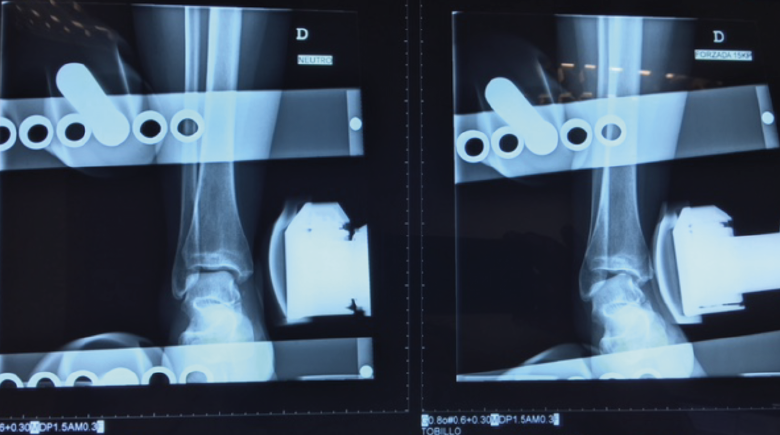

Radiologías forzadas

Se llevan a cabo con la intención de confirmar y cuantificar la laxitud.

Figura 3. Radiografía en varo forzado. Tienen valor diagnóstico si son positivas. El varo forzado es positivo si existe un varo > 15° o una diferencia de > 10° respecto al tobillo contralateral.

Presentan buena especificidad pero baja sensibilidad, por lo que solo tienen valor diagnóstico si son positivas:

- Varo forzado: positiva si existe un varo > 15° o una diferencia de > 10° respecto al tobillo contralateral (Figura 3).

- Cajón anterior: positiva si existe una traslación anterior > 1 cm o una diferencia > 3 mm respecto al tobillo contralateral (Figura 4).

Figura 4. Radiografía del cajón anterior. El cajón anterior es positivo si existe una traslación anterior > 1 cm o una diferencia > 3 mm respecto al tobillo contralateral.